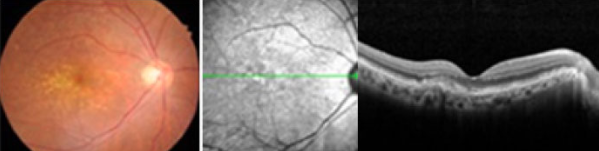

안저촬영 및 빛간섭단층촬영에서 보이는 건성 황반변성

망막에 드루젠이라는 지성 노폐물이 쌓이면 정상적으로 황반에 시상이

맺히는 것을 방해해 건성 황반변성으로 악화됩니다.

항산화제 복용, 금연, 자외선 노출 방지 등 악화를 최소화하는 예방법이 필요합니다.